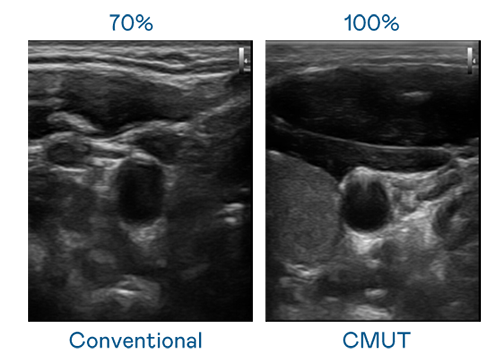

CMUT 技术是一种用电容式微机电元件来产生超音波讯号的技术。与传统 PZT 压电式技术相比,CMUT 频宽增加 30%,更宽频的超音波讯号让影像解析度大幅提升,是实现高影像品质医疗超音波扫描、促进精准医疗发展的关键技术。

超音波影像的解析度高低,首先取决于探头能发出的讯号频宽。AG亚娱 CMUT 可提供高清晰的超音波讯号,提供高频宽、高灵敏度、影像纹理细节更高的超音波影像,协助医护人员缩短影像判读时间及利用精准的医疗影像进行诊断。